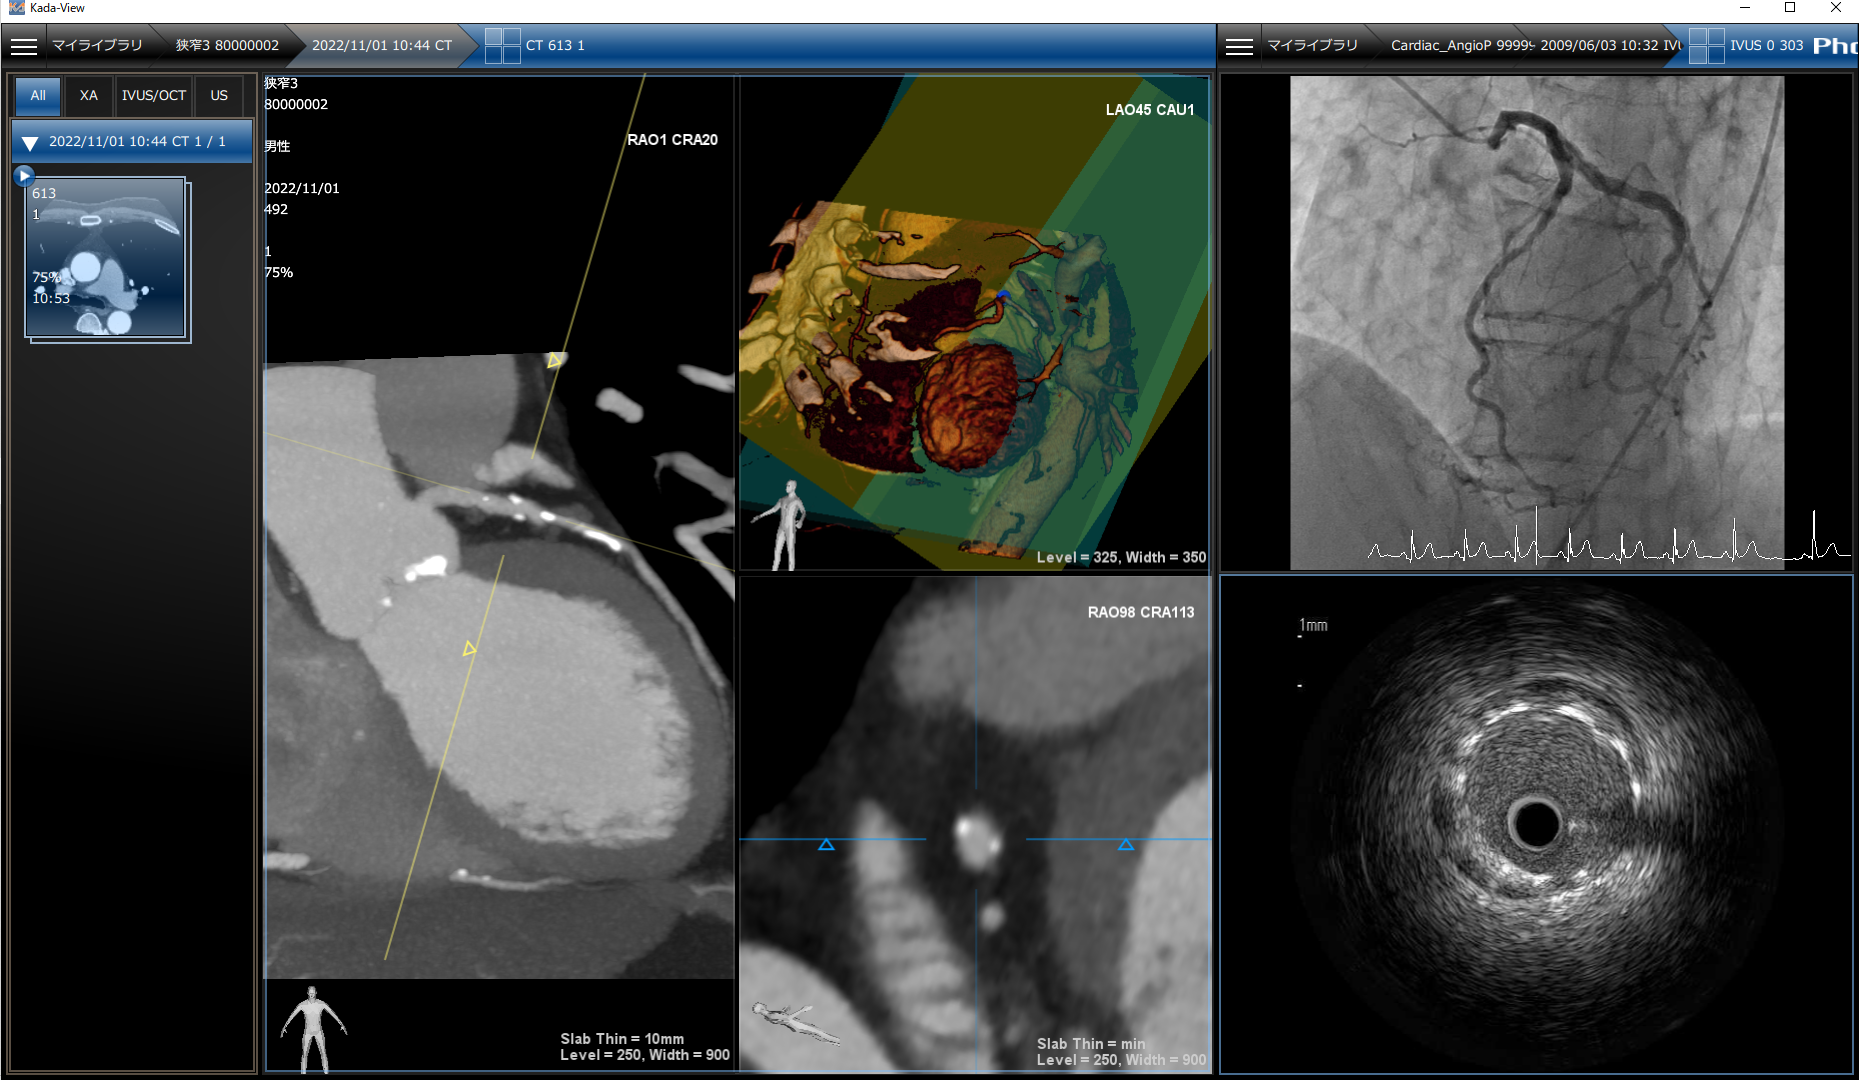

DICOM動画ビューワ『Kada-View』に新たに搭載されたCT Viewerオプションでは、Sliding slab MIP機能により冠動脈の近位部から遠位部までを迅速かつ簡便に連続して観察でき、カラーマップやグラデーションカラーマップ機能により病変性状を簡便に推測できる。

手技中に術前CT画像をAngio画像と同時に表示し、それを参考に病変の形状を確認しながらPCIを施行できる。

Angio、IVUS、US、CTなどDICOMデータを同時に表示し、適切に病変を観察できる。